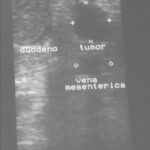

Los insulinomas aparecen característicamente como lesiones hipoecoicas, homogéneas y bien delimitadas en las imágenes de ultrasonido. Además, esta técnica permite diferenciar estas lesiones de otras patologías pancreáticas, como quistes o tumores sólidos no funcionales. La información proporcionada por la endosonografía es esencial para la evaluación prequirúrgica, ya que facilita la localización precisa del tumor y su relación con estructuras vasculares y conductos pancreáticos, optimizando así el abordaje quirúrgico.(9)

La ecografía es un método de mucha relevancia, complementario en el manejo del insulinoma. Permite, junto con la palpación bimanual, localizar la lesión señalada por los otros exámenes. Este método tiene una sensibilidad del 9%-64%, pero la combinación de la palpación del páncreas más la ecografía alcanza una sensibilidad del 100%, (7, 10) con limitaciones cuando se trata de tumores <2 cm.(6, 11)

Paciente masculino de 35 años de edad, con antecedentes de tabaquismo, etilismo, consumo de sustancias psicoactivas. Ingresa al hospital de Sanatorio Franchin el 24 de mayo de 2024, donde se constata hipoglucemia severa con buena respuesta al glucosado hipertónico endovenoso. Al examen físico con la típica tríada de Whipple, dado por síntomas neuroglucopénicos de alteración del estado de conciencia, glucemia de 25 mg/dl y alivio sintomático después de la administración de glucosa. El paciente recupera el estado de conciencia y refiere dolor abdominal a nivel de epigastrio, por lo que se le realiza ecografía abdominal, donde se evidencia lesión nodular hipoecogénica en cuerpo del páncreas. Por esta razón se pasa al paciente a tomografía, donde se constata una formación nodular a nivel del cuerpo del páncreas, que presenta un ávido realce en fase arterial con homogeneización de la lesión en tiempo tardío.

Una vez que tengamos una fuerte sospecha diagnóstica basada en la clínica y el laboratorio bioquímico viene la localización del tumor, que se puede realizar a través de métodos no invasivos, como la ecografía, que como método de abordaje inicial no está mal para una primera exploración, pero debemos conocer que su sensibilidad es muy baja, del 9%. Pero como un estudio no invasivo, rápido, relativamente económico, y si está disponible en nuestro servicio, se puede utilizar. Los insulinomas se pueden observar por este método como una imagen nodular hipoecogénica que puede mostrar ante la presencia de Doppler color un patrón periférico o centrípeto, porque recordemos que estos son tumores hipervasculares, lo que significa que tienen una alta densidad de vasos sanguíneos.